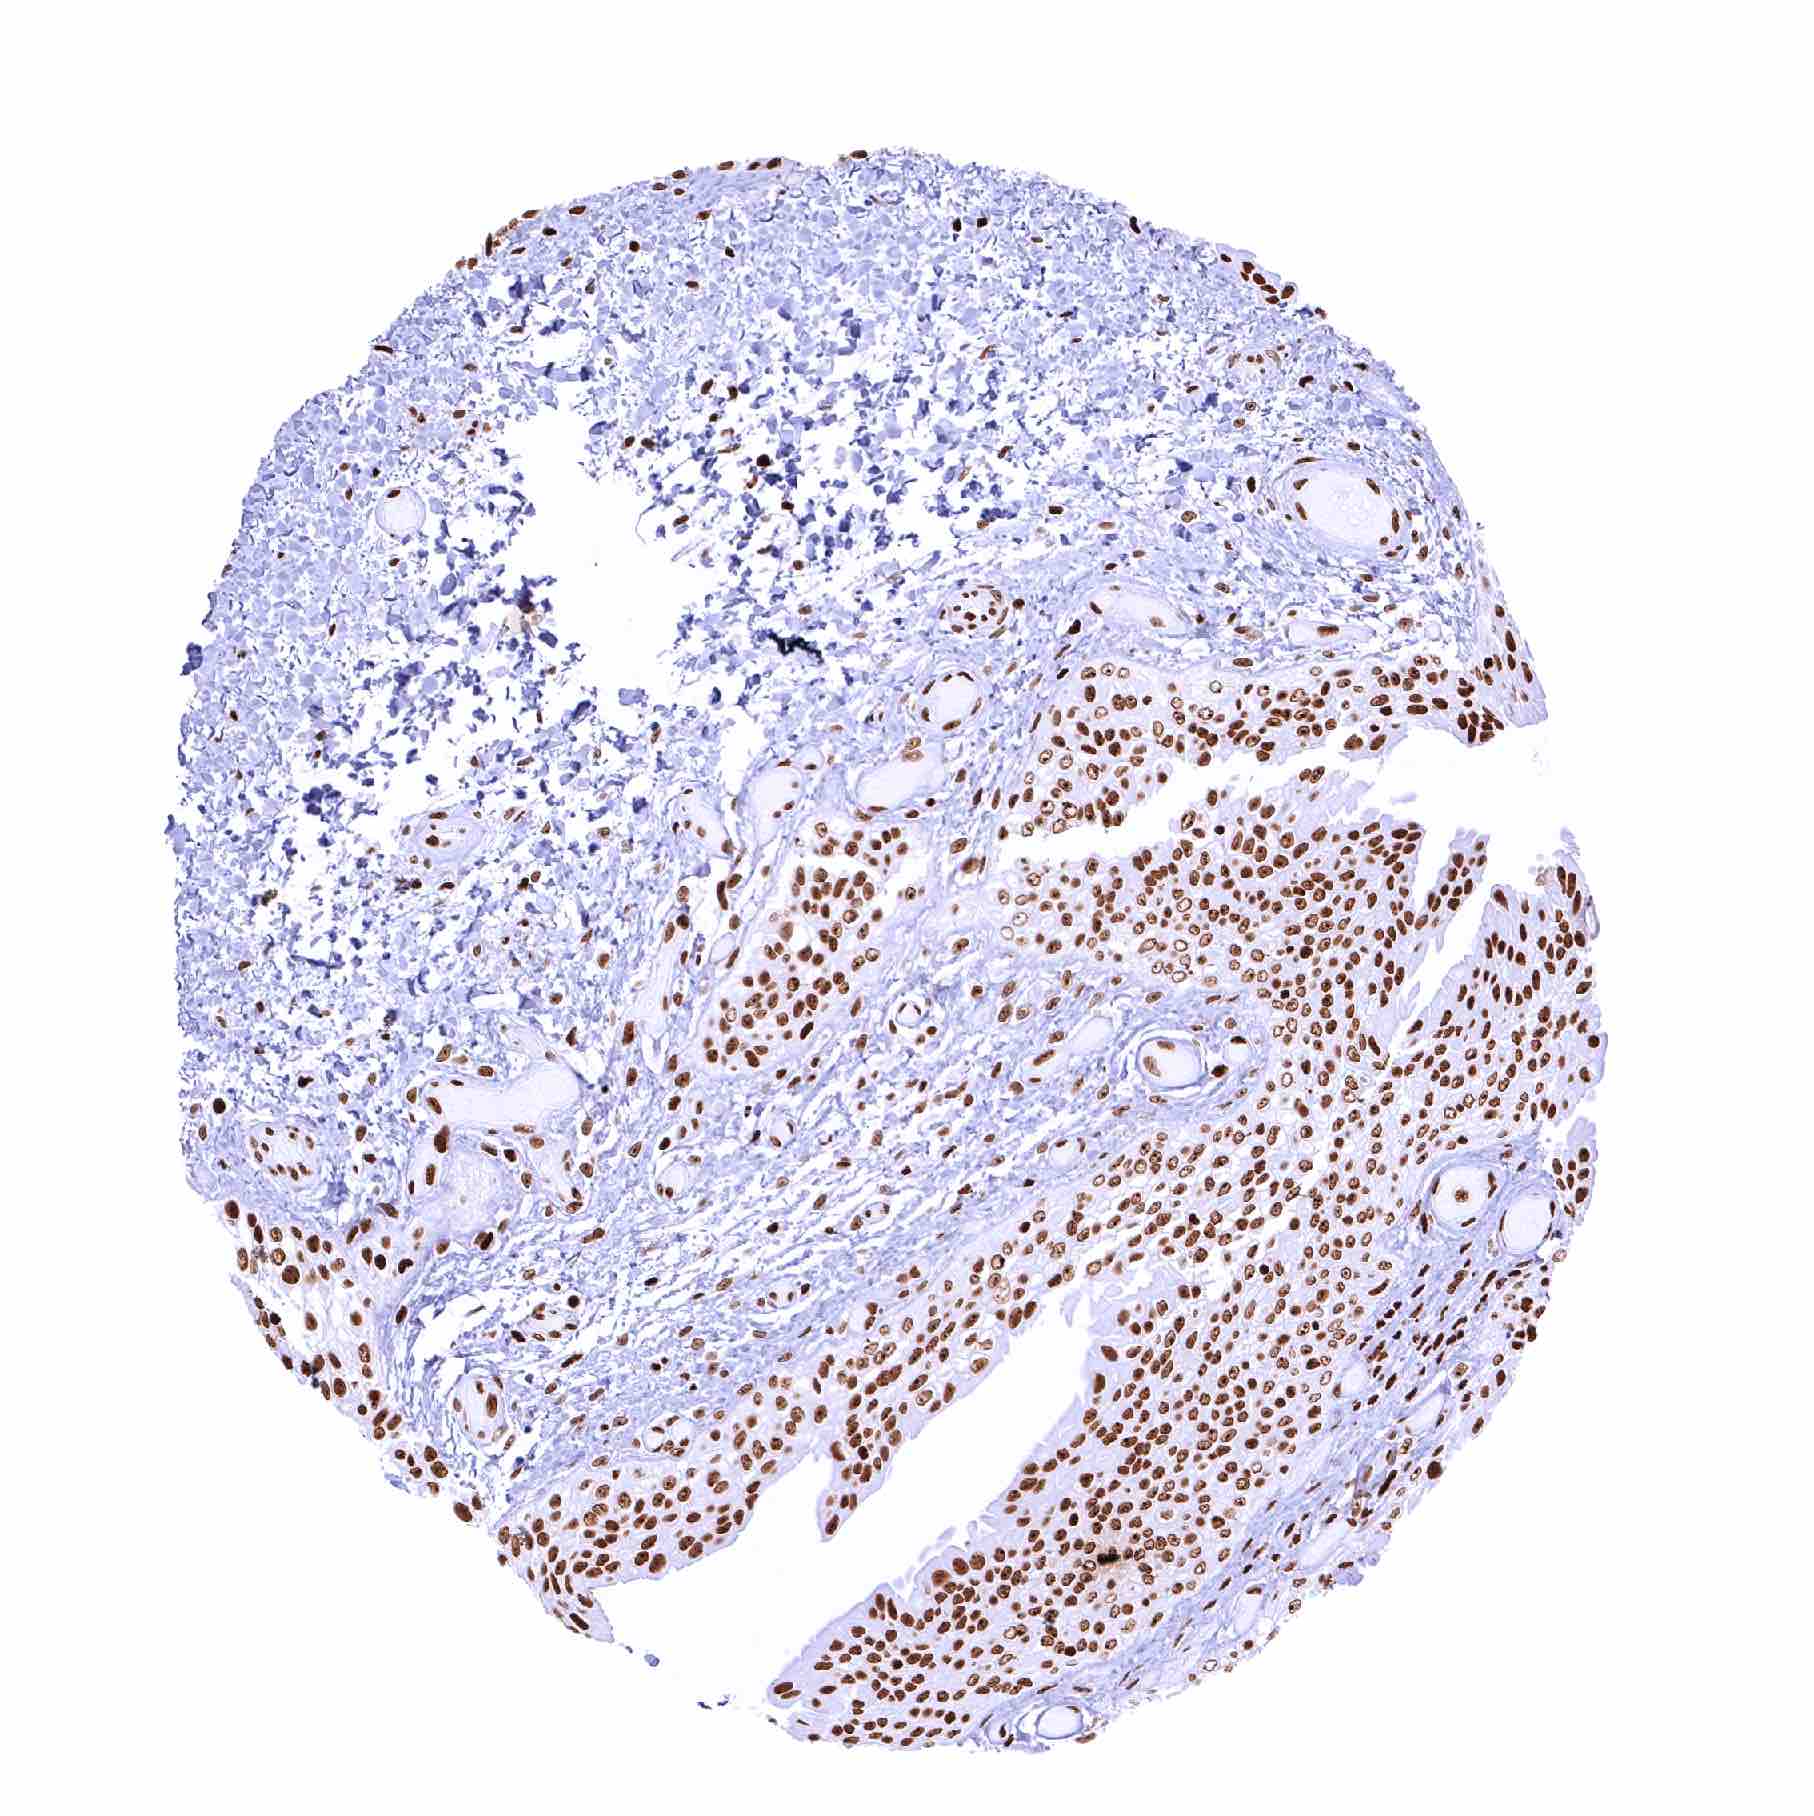

Placenta, early – Absence of PARP1 staining in the syncytiotrophoblast. Distinct PARP1 positivity of all other cells

Placenta, mature – Absence of PARP1 staining in the syncytiotrophoblast